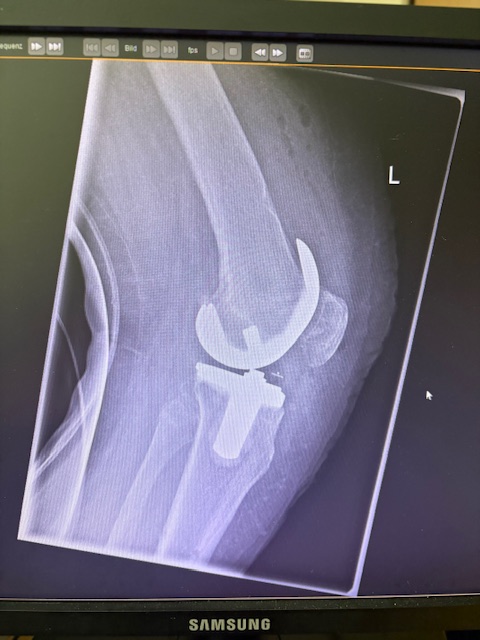

Τα εμφυτεύματα που χρησιμοποιήθηκαν στο γόνατο της ασθενούς είναι της Aesculap: E-Motion Pro, μηριαίο μέγεθος 4, κνημιαίο μέγεθος 4, με ενθέμα (inlay) 10mm.

Ήδη από τις πρώτες εβδομάδες, περπατούσε χωρίς πόνο, με βελτιωμένο εύρος κίνησης.   Η παθητική κίνηση κατα την έξοδο της ασθενούς από την κλινική ήταν E/F : 0-0-120 Επίσης πλήρη σταθερότητα του γόνατος σε κάμψη και έκταση.